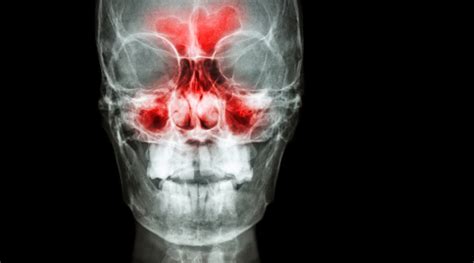

La sinusitis maxilar se trata de una inflamación de la mucosa que recubre los senos maxilares, una de las cavidades que conforma los senos paranasales, es decir, las cavidades aéreas que comunican con las fosas nasales. Asegurar el cuidado y bienestar de estos senos es fundamental ya que tienen importantes funciones a la hora de respirar, masticar, hablar u oler.

Los senos paranasales son unas cavidades que se encuentran en la cara. Son ocho en total y se sitúan cuatro a cada lado de la nariz. Dichos senos están, a su vez, formados por el seno frontal, el seno etmoidal, el seno maxilar y el seno esfenoidal.

En cualquier caso, lo que le sucede a una persona que padece sinusitis maxilar es que el aire no pasa con normalidad a través de los senos, ya que las cavidades se bloquean. La sinusitis maxilar es la inflamación -y obstrucción- de los senos paranasales, que son un conjunto de cavidades comunicadas con las fosas nasales.